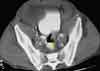

You order a CT scan with contrast to investigate theabnormality. An axial image at the level of the kidneysconfirms the presence of dilated bowel (B, arrow). Thereis no evidence of pneumatosis or bowel-wall thickening.An image at the level of the iliac crests shows a prominentgas-fluid level in the ascending colon, which would correlatewith an obstruction (C, arrow). This image also confirmsthat there are no dilated loops of small bowel. Athird CT image, at the level of the middle pelvis, revealscontrast in the bladder and rectum (D). Careful inspectionshows that the rectosigmoid junction has a "beaked"appearance (arrow).